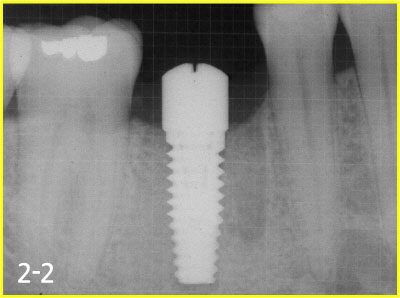

Placing implant

taking X-ray to secure safe implant surgery

Taking impression and fabricating implant crown 2-3 months after surgery